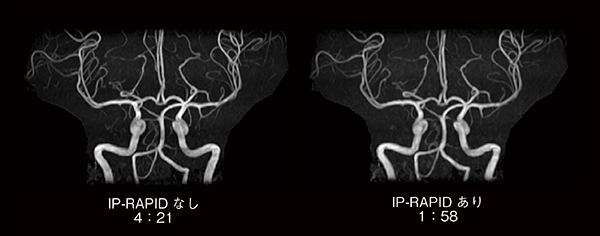

図3および図4は,従来のルーチンプロトコールと,IP-RAPIDを適用して撮像時間を短縮したプロトコールで撮像した,頭部T2横断像と頭部MRAのMIP画像の比較です。IP-RAPIDにより,同程度の画質ながら撮像時間がほぼ半分になっていることがわかります。撮像時間の短縮は検査時間全体の短縮に寄与し,被検者の心身的負担軽減が期待できます。一方,同じ撮像時間ならば,より分解能の高い画像を得ることが可能になると考えられます(図5)。ルーチン画像を短時間で取得することで検査時間枠に余裕が生まれ,異なる断面やシーケンスによる追加撮像が可能になると思われます。このように撮像時間の短縮は検査時間の短縮のみならず,検査内容の充実に対しても貢献し,被検者への手厚い医療が提供できると考えられます。

図4 MRA(MIP画像)におけるIP-RAPID有無の比較

撮像時間が半分以下においても,同等の画質が得られている。